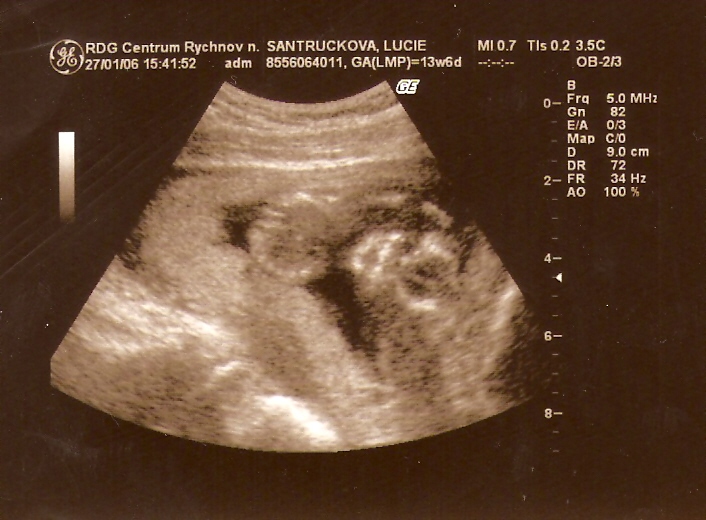

...27. LEDNA 2006 /14. týden/ mě poprvé viděli na ultrazvuku...zrovna jsem měl škitavku a pouhých 9 cm...